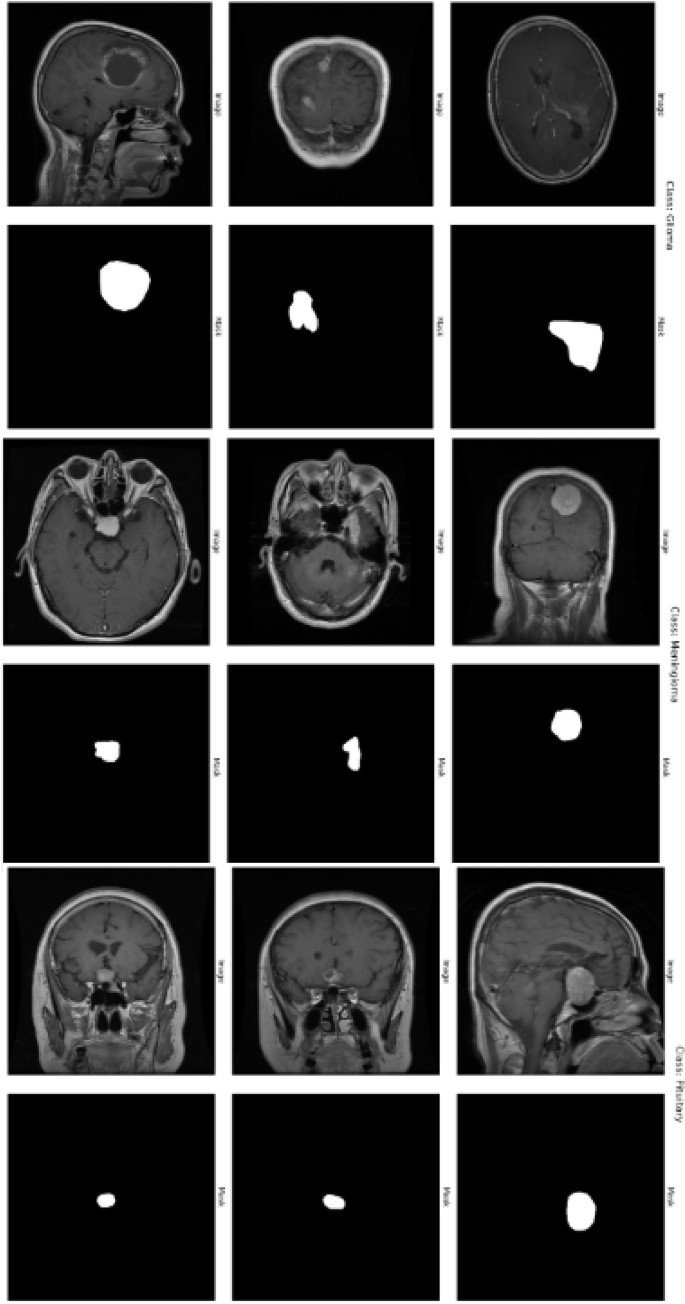

Preprocessing

Before training the model, several preprocessing steps are applied to the dataset. The raw images, initially in RGB color space, are first converted to the LAB color space to apply CLAHE (Contrast Limited Adaptive Histogram Equalization) to the L-channel. This step enhances the contrast of the images, especially in areas with low intensity. After CLAHE is applied, the image is converted back to BGR color space. Gaussian blur is then applied to the images to reduce noise and smooth out the image, improving the quality of the input data. The images are then resized to a consistent dimension of 256x256 pixels and normalized by dividing by 255, transforming the pixel values to the range [0, 1]. The grayscale images are resized to 256x256 pixels for the masks, normalized, and reshaped to include a single channel. The dataset is divided into training and testing sets with 90:10 split. Specifically, 90% of the samples are allocated for training the model, while the remaining 10% are set aside for testing and evaluating the model on unseen data. Figure 2 presents sample MRI images and their corresponding masks. Class-wise distribution of the dataset and data splitting ratio is provided in Table 2.

The dataset comprises a total of 3,064 brain tumor slices categorized into three classes: Glioma, Meningioma, and Pituitary Tumor. The dataset was split into 90% for training (2,758 images) and 10% for testing (306 images) to train and evaluate the proposed model. This stratified split ensures that each tumor category is proportionally represented in both the training and testing sets, facilitating robust model evaluation. The distribution of the three tumor types and data splitting ratio in the dataset is shown in Table 2. For each tumor type, images from three different planes-axial, sagittal, and coronal-are available. Sample images of each tumor type is illustrated in Fig.2